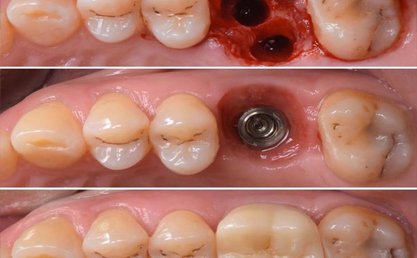

Teeth are given within a week after implant placement.

Implants are screw shaped that is placed in jawbone to replace a missing teeth. A crown is placed on this screw to look and function as the crown portion of the natural tooth. Dental implants are made majorly out of titanium material that suits the human body properly.